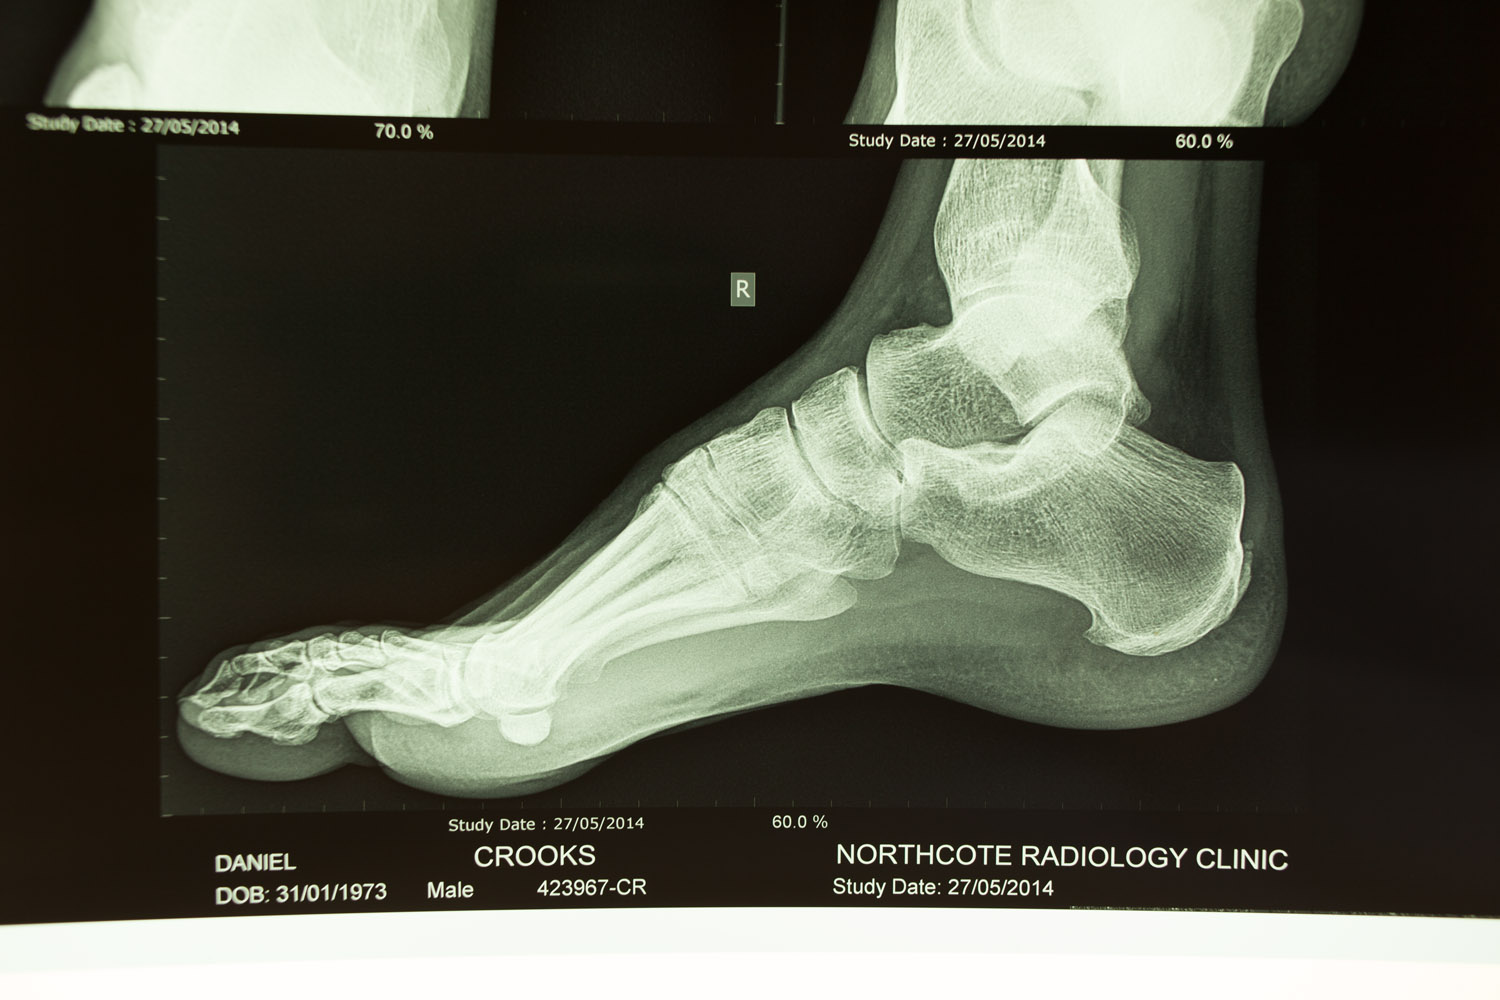

irrefutable evidence June 13, 2014injuryfucked, x-raystriker Almost a year later the foot is still sore, X-rays show “…early osteoarthritis involving the distal interphalangeal joint of the big toe and a fracture near the head of the proximal phalanx…”. Awesome.